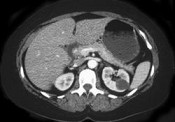

- 单项选择题女性,最近感腰部胀痛, 体检发现B超右肾正常,左肾有一囊肿, 双肾体积不增大,尿常规、肾功能正常, 无家族病史,CT表现如图所示, 最可能考虑为 ( )